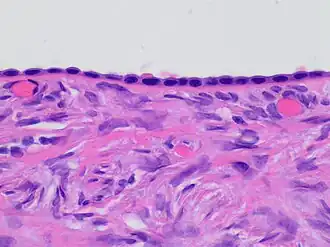

![]() Histology of ovarian surface epithelium. H&E stain. The epithelium is the chain-like covering with round dark blue nuclei at top. | |

The ovarian surface epithelium, also called the germinal epithelium of Waldeyer,[1] or coelomic epithelium, is a layer of simple squamous-to-cuboidal epithelial cells covering the ovary.[2]

These cells are derived from the mesoderm during embryonic development and are closely related to the mesothelium of the peritoneum. The germinal epithelium gives the ovary a dull gray color as compared with the shining smoothness of the peritoneum; and the transition between the mesothelium of the peritoneum and the cuboidal cells which cover the ovary is usually marked by a line around the anterior border of the ovary.